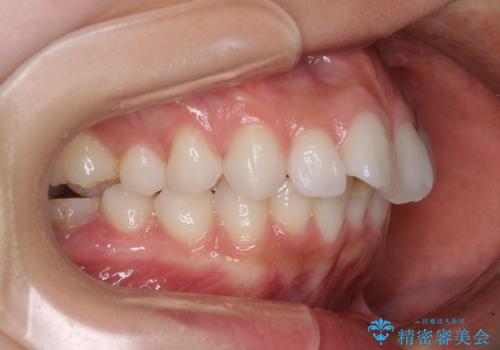

- 八重歯と叢生を気にして来院された患者様です。

上下の前歯が非接触であり、叢生や八重歯が顕著であったため、上顎左右第一小臼歯2本を抜歯して排列することとしました。

元々奥歯に負担のかかる咬み合わせですり減っていたため、仕上がった歯並びでも奥歯が咬んでいないように見えましたが、実際にはしっかりと咬合しており、患者様本人も咬んだ感触に違和感はないとのことでした。